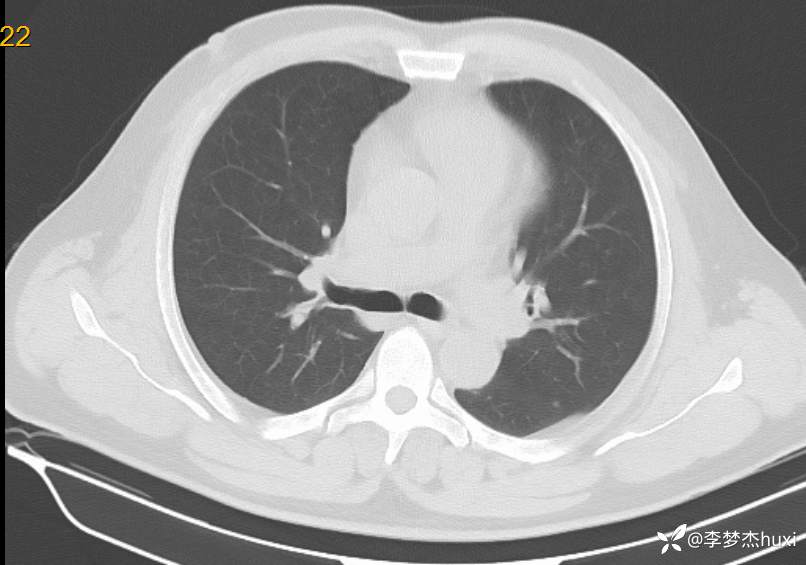

男性51岁,乏力伴胸闷、憋气4天入院,诊断可以秒杀且过目不忘

男, 51 岁,主因乏力伴胸闷、憋气4天于2024-06-11 11:57入院。

1.现病史:患者中年 男,患者缘于入院前4天无明显诱因出现乏力,伴胸闷、憋气,无咳嗽,咳痰,无发热,无咽痒,无咯血,无鼻塞、流涕,无发热,无恶心、呕吐,无腹痛、腹泻,无尿频、尿急、尿痛,无血尿及腰背部疼痛,院外查血常规:白细胞数目11.52x109/L,中性粒细胞百分比79.9%,血红蛋白69g/L。院外未服药治疗,症状无好转,现为求进一步诊治来诊,查肝胆胰脾肾彩超:脂肪肝(轻度),脾大。急诊以“低色素性贫血”收住院。。

患者诊断什么病?

精准诊断?